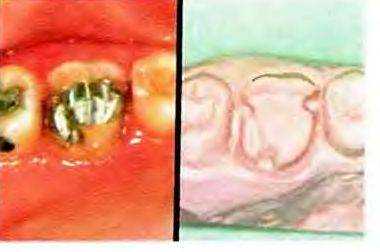

Рис. 5-52. Трехчетвертная коронка используется для восстановления моляра верхней челюсти после проведенного эндодонтического лечения и амальгамной реставрации (слева). Поскольку зуб имеет низкую клиническую коронку, то для повышения ретенции и устойчивости реставрации было решено использовать несколько ретенционных проточек. На гипсовой модели препарированного зуба эти детали хорошо видны (справа).